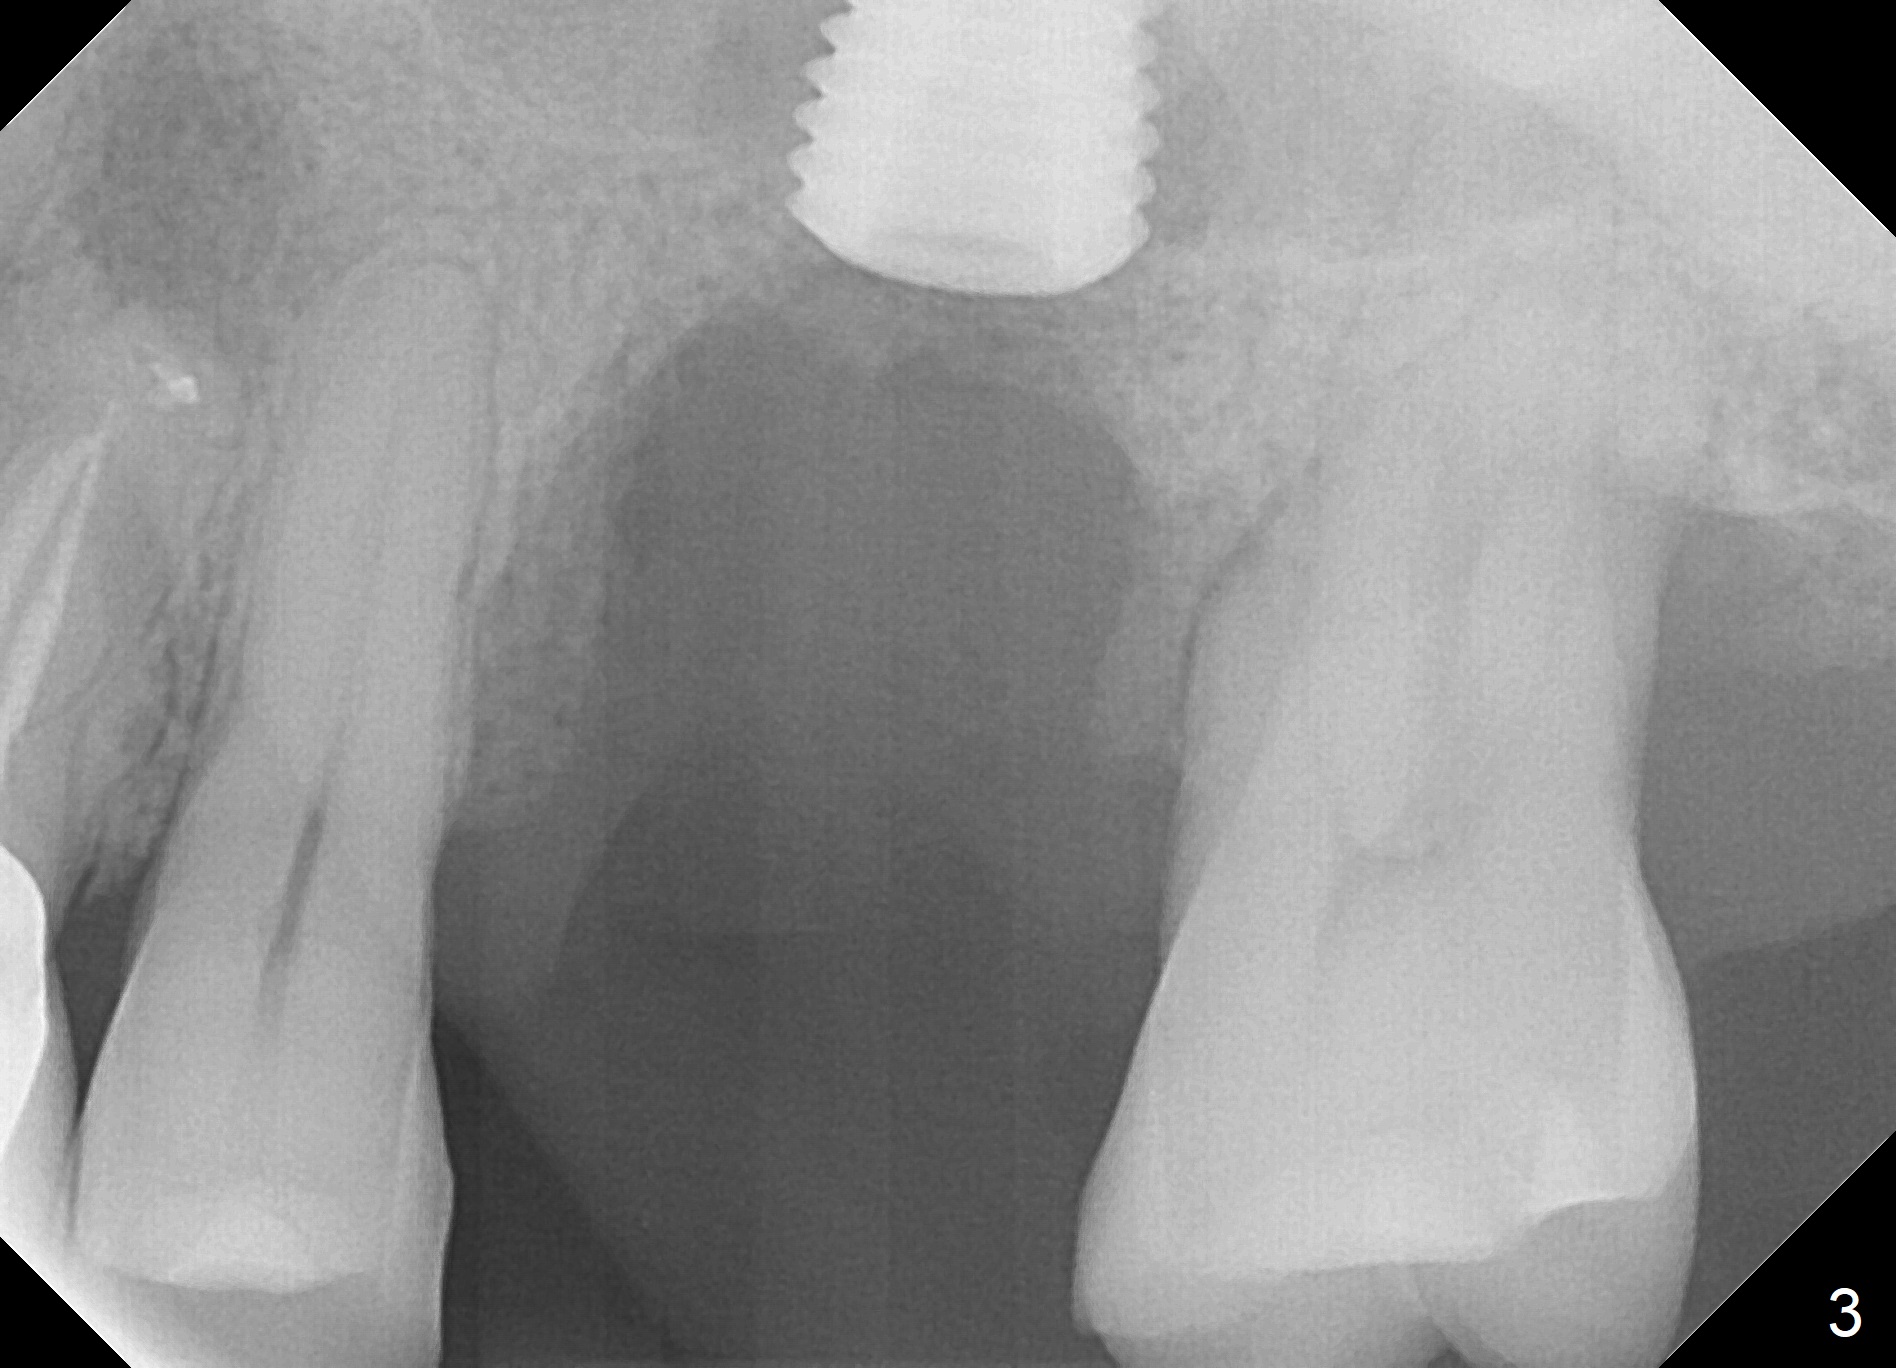

When the tooth #14 is extracted, the buccal plate is lost, while the apex of the palatal socket is perforated. The palatal slope of the septum appears to be a suitable site for osteotomy, but the depth seems to be 2 mm. After sequential osteotomy until 5.3 mm with drills, a 5.9 mm SM tap obtains stability (Fig.2). A 5.9x8 mmm implant is placed with barely sufficient stability after 1 piece of PRF membrane and VeraGraft (Fig.2-4). The implant rotates and dislodges when an abutment is being placed. Neither do 6-8x17 mm Tatum taps achieve primary stability. Socket preservation is performed, followed by periodontal dressing (Fig.5). Primary stability might have been obtained if a smaller IBS implant with fins were placed in the palatal socket. The periodontal dressing has dislodged 1 week postop; the socket appears healing (Fig.6,7). Bone graft seems to be minimal or bone density of the graft is low (Fig.8). The socket heals with a wide ridge 2 months post socket preservation, but the tooth #15 seems to be buccal (Fig.9) and mesial (Fig.10) shift. After use of Magic Split and Expanders (until 3.8 mm for 13 mm), try 5 mm dummy implant (Fig.11). If 6 mm one fails to achieve stability substantially, switch to 7 mm Tatum tapered tap provided there is enough mesiodistal space (use 8 mm implant positioner to gauze the space beforehand (preop)). Consider using Vanilla (not Vera) Graft to fill in the gap between implant and osteotomy. When primary stability is obtained, place a nonfunctional provisional to prevent further shifting (Fig.11 white outline). After osteointegration, use the provisional (reline and separator) to distalize the tooth #15.